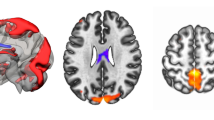

Functional connectivity

To assess the functional connectivity in each patient, preprocessed rs-fMRI and task data were first parcellated into 333 regions of interest (ROIs) according to the Gordon parcellation scheme (Gordon et al. 2016). These 333 parcels divide into 12 different functional brain networks, including the cingulo-opercular (CON), salience (SN), fronto-parietal (FPN), dorsal attention (DAN), ventral attention (VAN) and default mode (DMN) networks. The representative time series for each ROI were obtained by averaging the BOLD time series over the tumor-free extent of the parcel. For each patient and for both rest and task data, a weighted adjacency matrix was created by computing the correlation coefficient between every pair of nodes which were then Fisher transformed. The fully-weighted functional connectivity values were used rather than the binarized ones to conserve all connectivity information (Bassett et al. 2011; Vatansever et al. 2015; Zuo et al. 2018). From this correlation matrix (see Fig. 1a, b) we extracted nodes from our a priori networks to create network-specific graphs for the FPN (24 × 24) and the DMN (41 × 41). Additionally, we created an FPN-DMN graph (24 × 41) containing all connections between the 24 FPN regions and the 41 DMN regions. Consequently, we ended up with six (3 networks × 2 task states) graphs for each subject. Regions of the FPN or DMN that were fully covered by tumor mask on a subject level were excluded for that patient from our analyses. The resulting number of missing regions within the FPN or within the DMN due to tumor overlap was used as a covariate in our analyses.

a FPN (in red) and DMN (in yellow) regions defined according to the Gordon parcellation. b Correlation matrix for one subject in rest (left) and during the N-back task (right). Nodes 1 to 24 belong to the FPN network. Nodes 25 to 65 belong to the DMN network. c Definition of within- and between-network connections. Connections between nodes of the FPN (in red) and connections between nodes of the DMN (in yellow) are within-network connections. Connections between nodes of the FPN and nodes of the DMN (in black) are between-network connections

To quantify the communication abilities within and between networks, we computed the connection strength (Zuo et al. 2018) for each of these six graphs (see Fig. 1c). This connection strength is defined as the mean of the absolute values of all connections in a graph. As a measure of change from rest to task, we computed the ratio between the connection strength for the task graphs and the connection strength for the rest graphs.